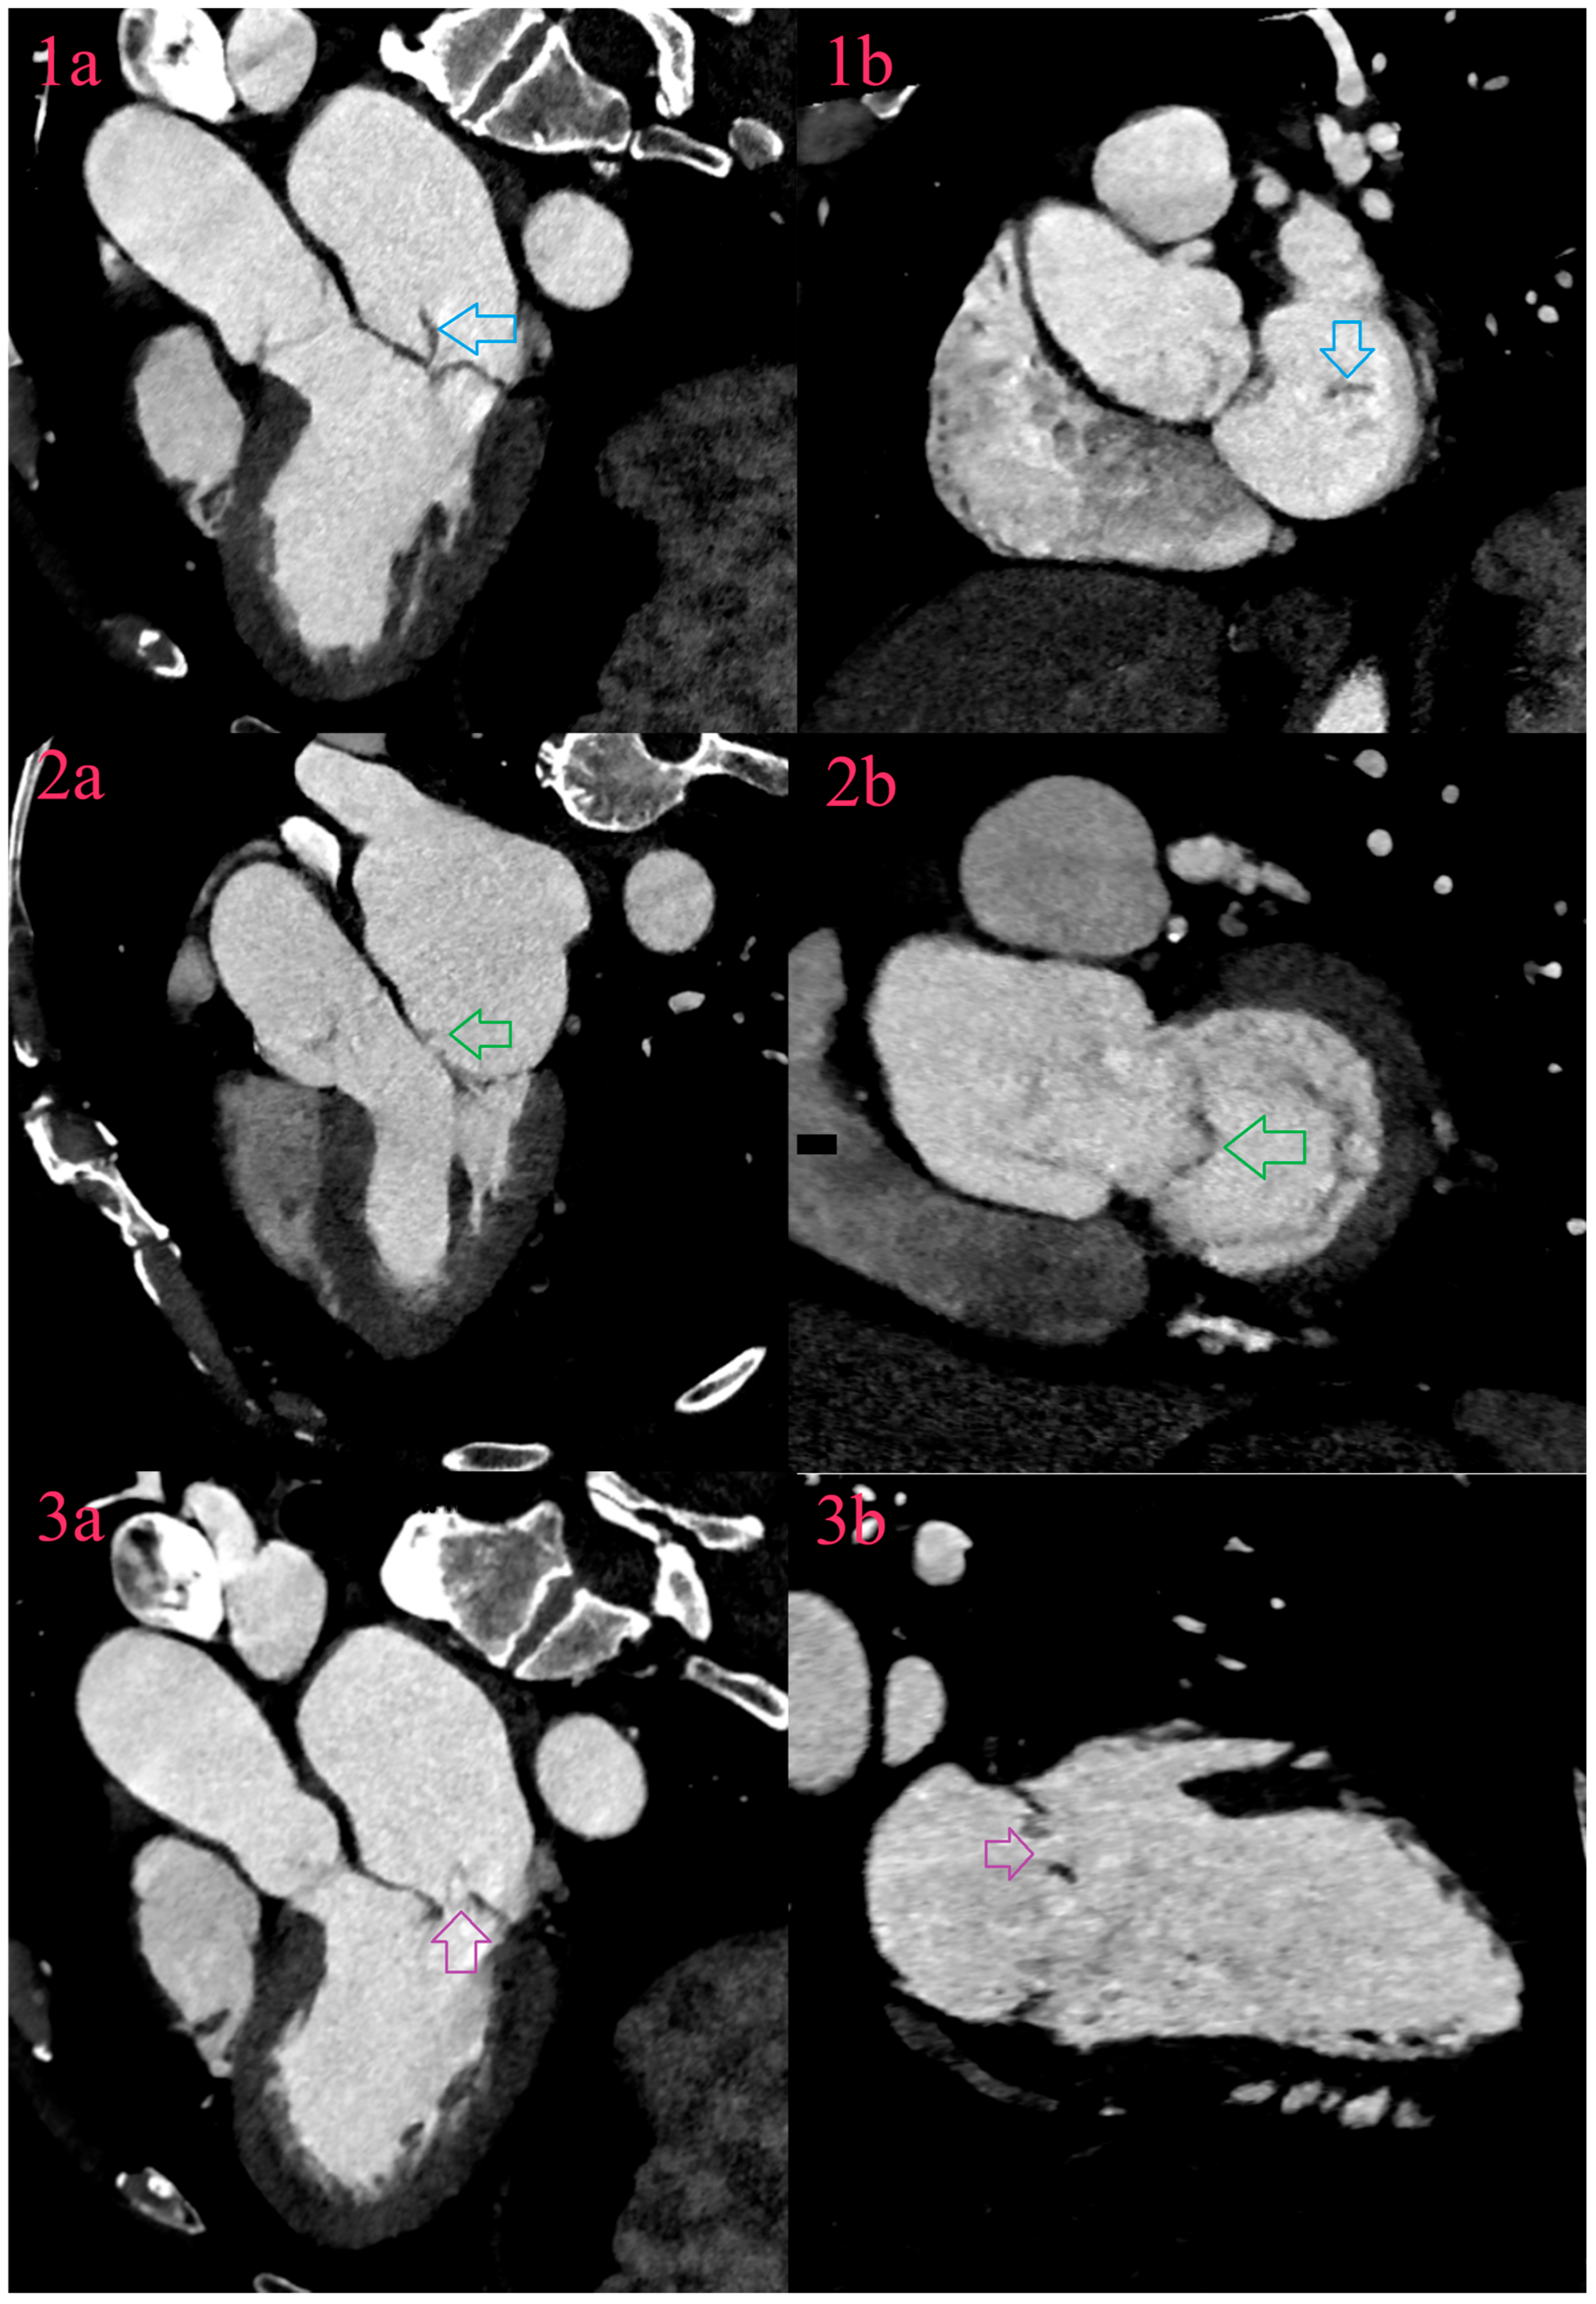

Figure 3.

Valvular lesions of IE of mitral valve. There is vegetation arising from free margin of posterior leaflet (Image 1a and Image 1b, blue arrow), aneurysm of anterior leaflet in A2 segment (Image 2a and Image 2b, green arrow) and perforation of aneurysm on the field of prolaps of P2 segment of posterior leaflet (Image 3a and Image 3b, purple arrow).

6.3. Perforations

A perforation is loss of leaflet continuity, due to tissue necrosis caused by bacterial enzymes, and may be associated with severe valve regurgitation. Echocardiography with the additional use of color Doppler effect, detects two jet phenomena as a sign of perforation. CCT detects perforation as a defect that needs to be confirmed in longitudinal and transversal valve-planar reformation (Figure 2) [31,32].